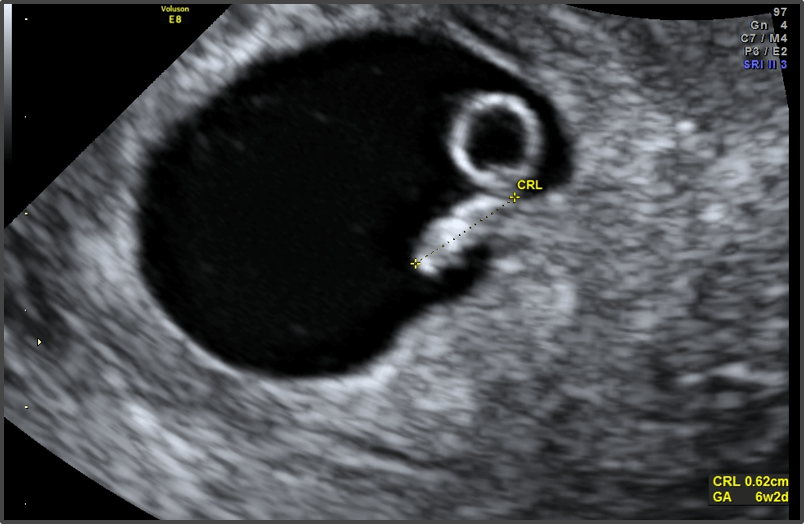

Baby is the size of Lentil

Approx Baby Weight: 1g

Approx Baby Size: 4-5 mm